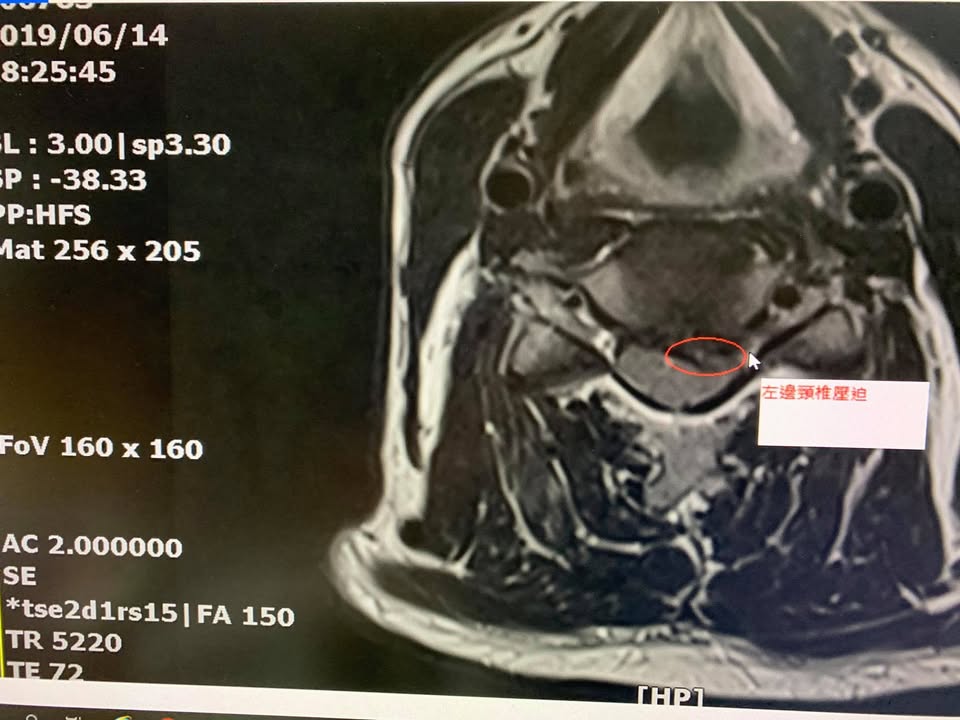

住在宜蘭的黃先生抱怨左邊頸椎痛連上臂,這兩個月嚴重惡化,今年六月十四號去陽明大學附設分院拍攝核磁共振,mri證實c4c5椎間盤突出壓迫脊髓,骨科醫師強烈建議開刀處理,門診檢查發現頸椎稍微往後仰立刻誘發麻痛,仔細詢問肩頸已經痛很長一段時間了,一直到今年才受不了,工作的時候很明顯感覺肩膀痛到手臂來,之前接受骨科小診所復健拉脖子拉了一年以上,效果還是不如預期,這次原本安排七月四號要開刀,在七月二號來到診所接受脊椎整合中醫微創療法,徐醫師告訴他如果前面兩三次治療有改善,前面兩三次就有改善可以跟醫院再延緩一段時間再開,非常幸運跟順利,到了第五次治療後有明顯突破,肩頸疼痛大幅度下降,黃先生直接將手術大刀取消掉,徐醫師囑咐他這次好了不代表以後永遠會好,重點是姿勢跟工作時間,更要好好訓練頸椎的力量!這樣才能永保安康

診斷:頸椎第四第五椎間盤壓迫硬膜囊

跟神經根